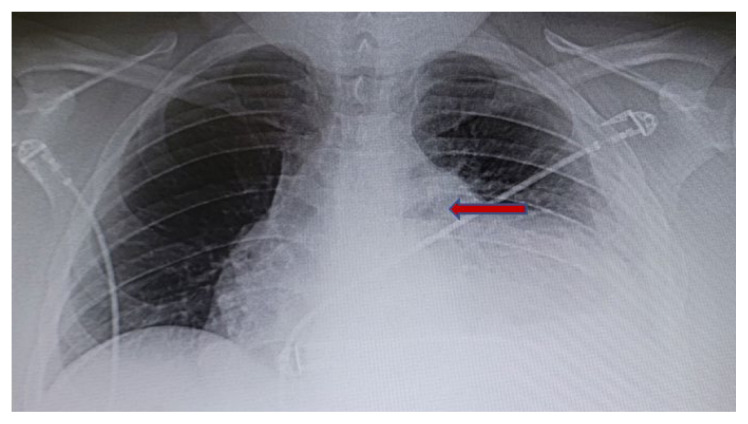

Over the next two days, the patient made minimal improvement clinically. A repeat chest x-ray showed a moderate left-sided pleural effusion and cardiomegaly (Figure 1). Thoracentesis was ordered, but ultrasound showed there was not enough pleural fluid to be drained. There was a concern for immunodeficiency with repeated infections and pneumonia. Blood and sputum cultures were negative.

Figure 1.

Chest x-ray showed cardiomegaly due to pericardial effusion.